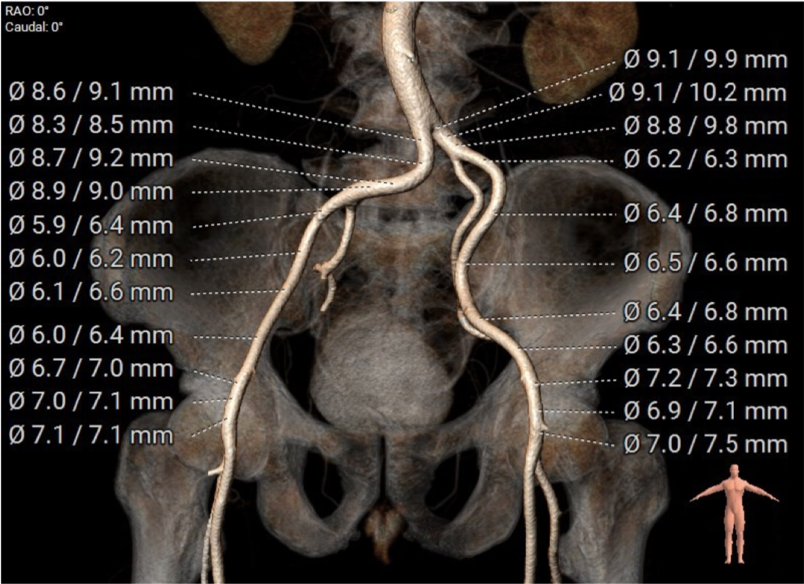

此患者解剖结构复杂:1)升主动脉明显增宽,平均直径达到54.5mm。

该结构需谨慎评估血管夹层和破裂风险,对瓣膜系统的通过性能要求极高。